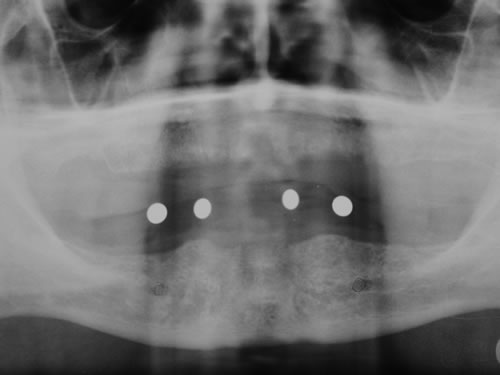

Die zahnärztliche Untersuchung umfasst die Beurteilung der gesamten Mundhöhle, der Schleimhaut, der Zähne und der Kieferknochen. Wenn eine Einpflanzung in Erwägung gezogen wird, muss eine Röntgenmessaufnahme angefertigt werden. Dazu wird nach einem Kieferabdruck eine Planungsschablone hergestellt, in die Metallkörper (Kugeln oder Stifte) an den Stellen eingearbeitet sind, an denen eine Implantation geplant ist (Abb. 5.1, 5.2). Diese Platte wird in den Mund des Patienten eingesetzt und die Röntgenaufnahme angefertigt (Abb. 5.3, 5.4).

Abb. 5.3: Eingesetzte Planungsschablone vor dem Röntgenbild.

Abb. 5.4: Kugelmessaufnahme zur Planung der Implantatlängen.

Abb. 5.5: Vermessen des Kiefers in mit speziellem Computerprogramm.

Da die Größe der Metallkörper, die auf der Aufnahme gut sichtbar sind, bekannt ist, kann aus dem Röntgenbild die zur Verfügung stehende Knochenhöhe sehr genau errechnet werden.

Mit der Entwicklung der Computertomographie (CT) und in jüngerer Vergangenheit der digitalen Volumentomographie (DVT) stehen Untersuchungsverfahren zur Verfügung, mit denen sehr viel einfacher und genauer das Knochenangebot vermessen werden kann. Von dem Patienten wird in einer Klinik oder Praxis, die über die entsprechenden Möglichkeiten verfügt, ein Spezialröntgenbild (DVT/CT) des Ober-, seltener des Unterkiefers, angefertigt. Dieses spezielle Röntgenbild dauert für einen Kiefer 20 Sekunden. Der große Vorteil liegt darin, dass der gesamte Kiefer durch den Computer in über 100 Schnitten abgebildet werden kann. Auf diesen Schnittbildern können Höhe und Breite des Knochens direkt abgemessen werden (Abb. 5.5).

Bei der ersten Untersuchung in der Praxis hat Frau W. zunächst den Anamnesebogen ausgefüllt. Sie ist nie ernstlich krank gewesen und nimmt nur gelegentlich eine Kopfschmerztablette. In einem ausführlichen Gespräch berichtet sie ihrem Zahnarzt über die Schwierigkeiten mit den Prothesen. Nach einer ersten Untersuchung kann ihr der Zahnarzt Mut machen. Die Kieferverhältnisse sind zwar sehr ungünstig, doch so, dass eine Einpflanzung noch möglich ist. Die vorhandenen Prothesen weisen keine Mängel auf, finden aber keinen Halt. Beide Prothesen sollen nach der Einpflanzung weiter getragen werden. Nach einem Kieferabdruck wird eine Platte für den Unterkiefer angefertigt, auf der Metallkugeln befestigt sind. Sie wird wie eine Prothese eingesetzt, und es wird eine Röntgenaufnahme gemacht, die anschließend vom Zahnarzt genau vermessen wird. Es ergibt sich, dass noch eine Resthöhe von 15 mm vorhanden ist. Da auch die Breite des Kiefers ausreicht, wird ihr die Einpflanzung von vier künstlichen Zahnwurzeln empfohlen. Für ihre spezielle Kieferform ist dies die beste Lösung.